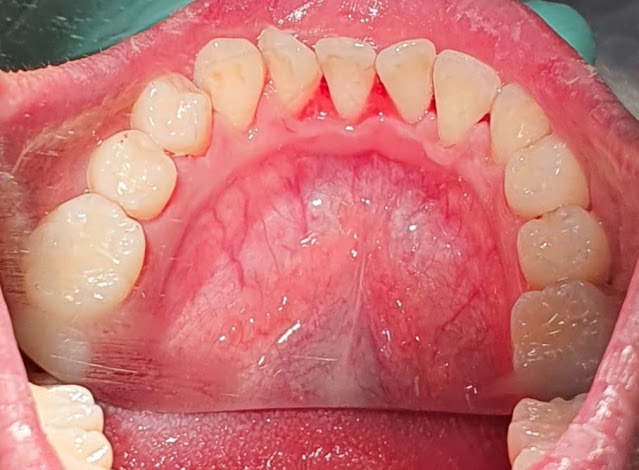

Ini penampakan gigi sebelum ditambal.

Ini foto gigi setelah ditambal.

Secara umum, penyebab gigi depan patah adalah trauma atau benturan. Biasanya juga terjadi akibat sering mengunyah makanan yang keras. Kebiasaan-kebiasaan ini bisa merusak mahkota gigi hingga berdampak pada gigi patah. Jika kerusakan gigi tergolong ringan, sebatas merusak lapisan enamel gigi, perawatannya pun cukup dengan tambalan sewarna gigi. Biasanya bahannya adalah komposit resin. Ada juga bahan-bahan lain seperti logam, amalgam, dan porselen.

Proses menambal gigi yang patah juga cukup dilakukan dalam satu kali kunjungan (jika kerusakannya tidak parah). Gigi yang patah direkatkan dengan tambalan berupa komposit yang warnanya menyerupai warna gigi. Tambalan ini akan mengeras dengan menggunakan sinar ultraviolet. Proses ini mungkin akan menimbulkan sedikit ngilu. Junisatya hanya perlu menghindari makanan panas dan dingin selama 24 jam setelah penambalan, agar tidak tambalan mengeras dengan sempurna di gigi.